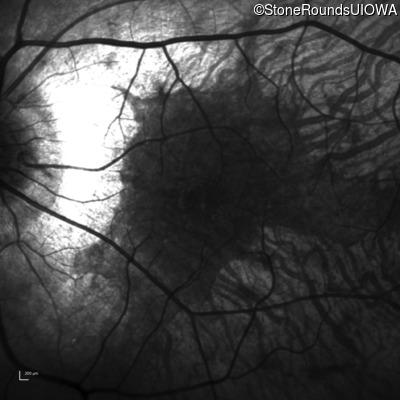

Infrared Fundus Photograph - Right - 20/20

Exemplar

Infrared Fundus Photograph - Left - 20/20